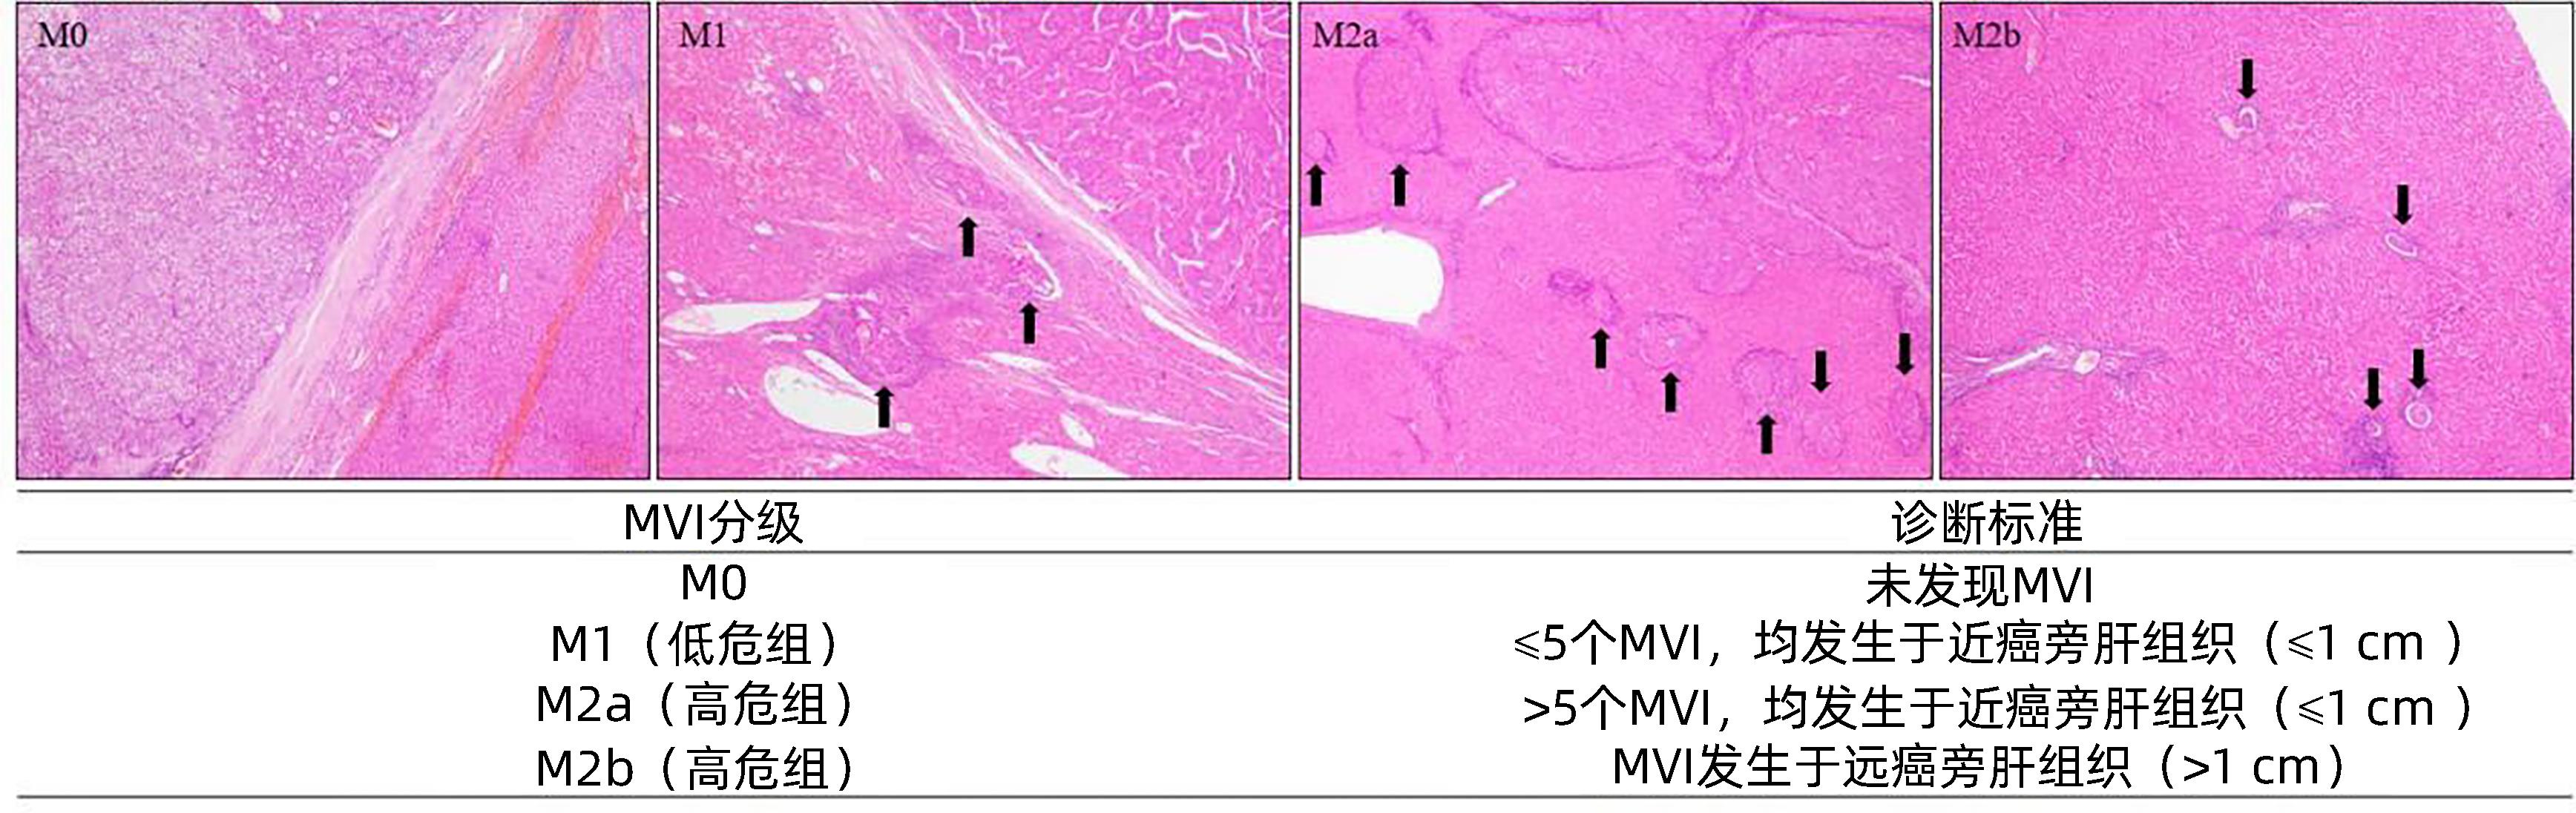

Standard for diagnosis and treatment of primary liver cancer (2024 edition)

2024, 40(5): 893-918. DOI: 10.12449/JCH240508